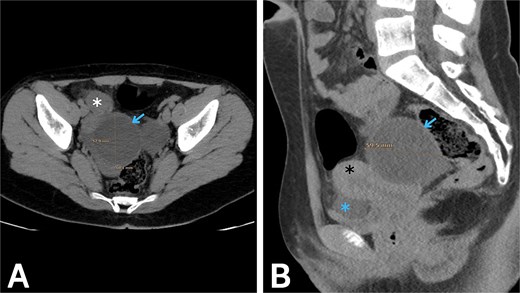

Initial laboratory testing showed mild leukocytosis with neutrophilia, while urinalysis was normal. Because the clinical pattern raised concern for acute appendicitis, imaging was pursued. Transabdominal ultrasound (US) showed a normal caliber gas-filled appendix, and a normal uterus and ovaries but showed a hypoechoic cyst measuring approximately 6*6 cm adjacent to the right ovary, with a tortuous and thickened tubular structure visualized between the cyst and the ovary. Doppler assessment showed preserved blood flow to both ovaries. Given the continuing diagnostic uncertainty, an abdominopelvic computed tomography (CT) scan without contrast was obtained (Fig. 1), which revealed a cystic structure measuring roughly 6 × 5.8 cm in the right adnexal region, consistent with a POC, with features concerning for torsion and a small amount of free fluid in the pelvis. Correlating the imaging with the clinical course raised strong suspicion of IFTT secondary to the POC.

Abdominopelvic CT without contrast. (A) Axial and (B) sagittal images show a right paraovarian cystic lesion (blue arrow) measuring approximately 6 × 5.8 cm, associated with a small volume of pelvic free fluid (blue asterisk). The right ovary (white asterisk) and the uterus (black asterisk) are also seen.